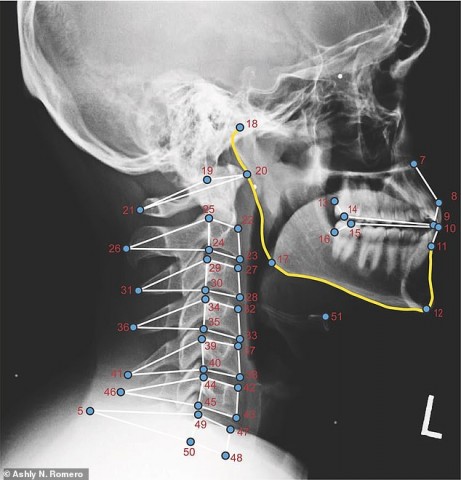

По словам исследователей, проблемы связаны с положением шеи во время использования смартфонов, особенно при рассматривании экрана устройства. В связи с тем, что обычно у мужчин шея длиннее, они сгибают её у самой головы. А вот у женщин зона изгиба приходится ближе к грудной клетке.

Получив серию рентгеновских снимков от группы пациентов, в которую входили и мужчины, и женщины, учёные пришли к выводу, что последние, смотря на экран смартфона, нетипично опускают глаза вниз и выдвигают голову немного вперёд. Это приводит к излишней нагрузке на шейные позвонки и вызывает болевые ощущения в шее и челюсти.